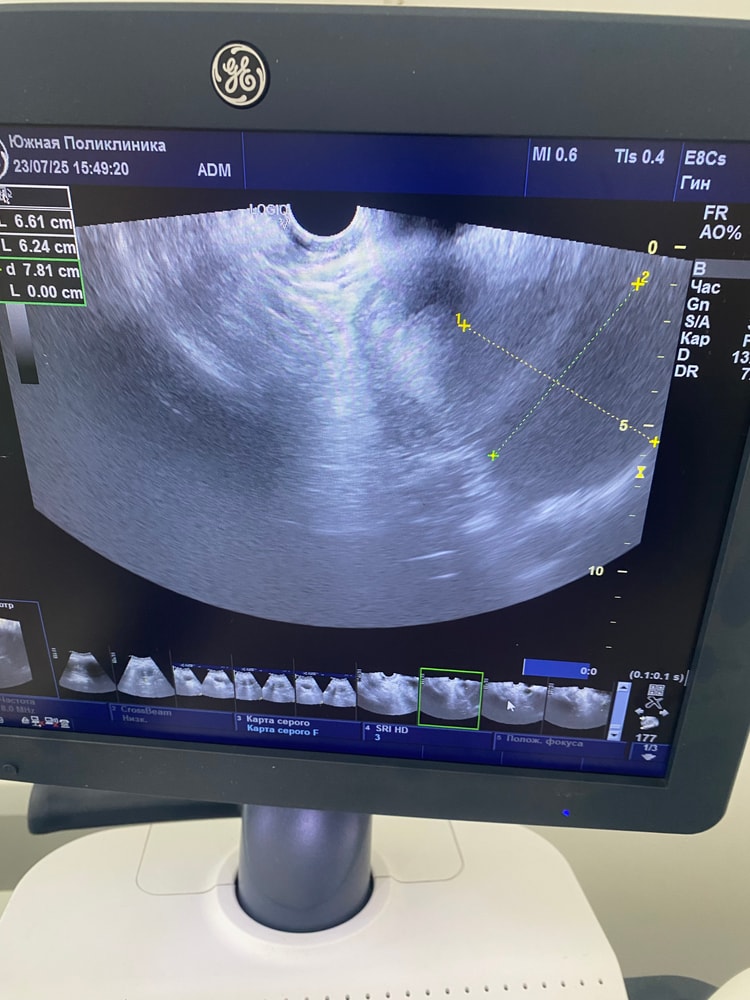

Гинекологические заболеванияНачну с того, что делала фолликулометрию и на 13 ДЦ фолликул был 1,5 см. Ждала овуляцию, с 16 дц начались какие то боли как при О, но не прошли в тч 1-2 дней. Сегодня на 20ДЦ пошла на узи, нашли какую то кисту, вроде с перегородками она сказала. Или с чем то на букву «П». Могу путать. Размер 4.5 см. Желтого тела нет, фолликула моего того тоже нет. Откуда эта киста взялась если её не было неделю назад? Заключения нет, есть фото. Девочки кто разбирается, посмотрите пожалуйста 🙏🏻

врач в ЖК сказала просто наблюдать, это обычная киста которая бывает у всех. Но она не знает что киста с перегородками. А чат gpt выдал что это не хорошие признаки(((